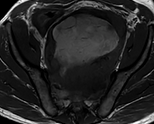

After opening of the specimen, the peripheral solid component and the central cystic component are demonstrated (blue arrow) (Courtesy Dr. V. Penopoulos)

The cystic part of the tumor contained a pale-yellow, thin fluid, odorless and sterile (Courtesy Dr. V. Penopoulos)